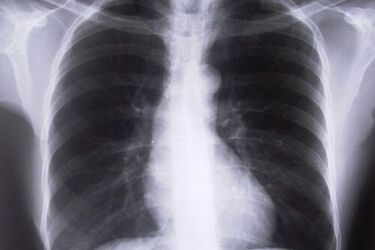

Bezpłatne badania spirometryczne i konsultacje lekarzy w Białymstoku

Już w poniedziałek (4.11) białostoczanie będą mogli wykonać bezpłatne badanie spirometryczne, a w razie potrzeby także skorzystać z porady lekarza specjalisty, który dokona analizy wyniku badania.

Badania i konsultacje odbywają się w ramach programu edukacyjnego "Chwytaj każdy oddech". Celem programu jest edukacja pacjentów i ich rodzin w zakresie chorób płuc. Szczególną rolę odgrywa tutaj profilaktyka, wczesna diagnostyka i zasady współpracy pacjenta i lekarza w trakcie leczenia astmy i POChP. Program wsparli wybitni eksperci w dziedzinie chorób płuc.

Bezpłatne badania spirometryczne i konsultacje lekarzy specjalistów odbędą się w poniedziałek (4.11) w Poradni Alergologicznej E. J. Botulińska, A. Płoszczuk, A. Trofimowicz SP. J. przy ul. Przejazd 2A w Białymstoku.

Badania będą wykonywane w godz. 15.00 – 19.00.